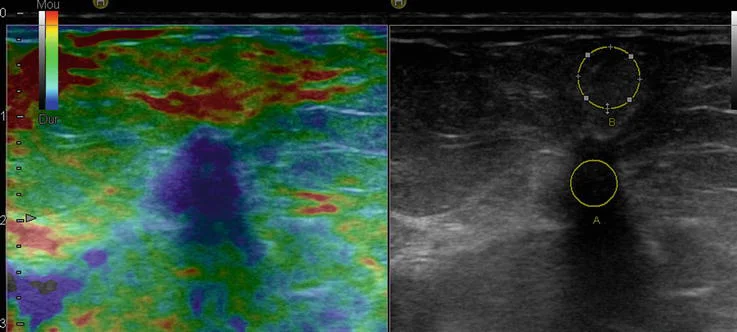

The ultrasound system evaluates how much the breast tissue compresses or moves in response to gentle pressure (or shear waves).

• Soft tissue = likely benign

• Hard/stiff tissue = needs further evaluation

A color-coded stiffness map is added to your ultrasound images for more precise evaluation.